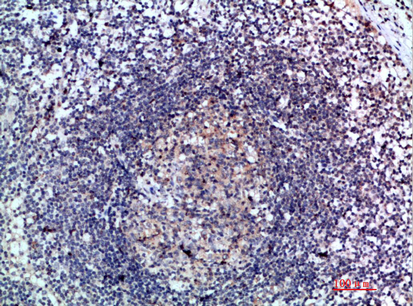

Immunohistochemistry analysis in human lymph node and cerebral cortex tissues using HPA051210 antibody. Corresponding CCL21 RNA-seq data are presented for the same tissues.